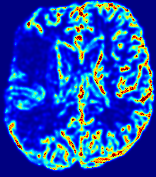

LesionRefer to captionRefer to captionRefer to captionRefer to captionRefer to captionRefer to caption𝐕rgbsubscript𝐕𝑟𝑔𝑏{\bf{V}}_{rgb}Refer to captionRefer to captionRefer to captionRefer to captionRefer to captionRefer to caption𝐕2subscriptnorm𝐕2{\|\bf{V}}\|_{2}Refer to captionRefer to captionRefer to captionRefer to captionRefer to captionRefer to captionRefer to caption3.53.53.52.82.82.82.12.12.11.41.41.40.70.70.70.00.00.0(mm/s)𝑚𝑚𝑠(mm/s)D𝐷DRefer to captionRefer to captionRefer to captionRefer to captionRefer to captionRefer to captionRefer to caption0.0200.0200.0200.0160.0160.0160.0120.0120.0120.0080.0080.0080.0040.0040.0040.0000.0000.000(mm2/s)𝑚superscript𝑚2𝑠(mm^{2}/s)Slice #1Slice #2Slice #3Slice #4Slice #5Slice #6

Figure 3: PIANO feature maps for one stroke patient, where the lesion is located in the left hemisphere. Top row: segmented stroke lesion region (white) on different slices, obtained from ISLES 2017. The corresponding slices for the PIANO feature maps are shown in the following rows.

For a better insight into an estimated velocity field 𝐕𝐕{\bf{V}} and diffusion field 𝐃𝐃{\bf{D}}, we compute the following maps: (1) 𝐕rgbsubscript𝐕𝑟𝑔𝑏{\bf{V}}_{rgb}: Color-coded orientation map of 𝐕=(Vx,Vy,Vz)T𝐕superscriptsuperscript𝑉𝑥superscript𝑉𝑦superscript𝑉𝑧𝑇{\bf{V}}=(V^{x},V^{y},V^{z})^{T}, obtained by normalizing 𝐕𝐕{\bf{V}} to unit length and mapping its 3 components to red, green, blue respectively; (2) 𝐕2subscriptnorm𝐕2\|{\bf{V}}\|_{2}: 222 norm of 𝐕𝐕{\bf{V}}; (3) D𝐷D: scalar field in Eq. 5.

Fig. 3 and Fig. 4 show the PIANO feature maps estimated from two ISLES 2017 patients: all are highly consistent with the lesion in both cases. Details of the blood flow trajectories are revealed in 𝐕rgbsubscript𝐕𝑟𝑔𝑏{\bf{V}}_{rgb} by the ridged patterns and the sharp changes of colors in the unaffected (right) hemisphere, while the flat patterns appearing within the lesion provide little directional information about the velocity and indicate low velocity magnitudes. Velocity magnitudes are more directly visualized via 𝐕2subscriptnorm𝐕2\|{\bf{V}}\|_{2}, from which one can easily locate the lesion where 𝐕2subscriptnorm𝐕2\|{\bf{V}}\|_{2} is low. D𝐷D also indicates lower diffusion values in the lesion, though with less contrast potentially due to the fact that it captures the accumulated effect of CA diffusion at the voxel-level.